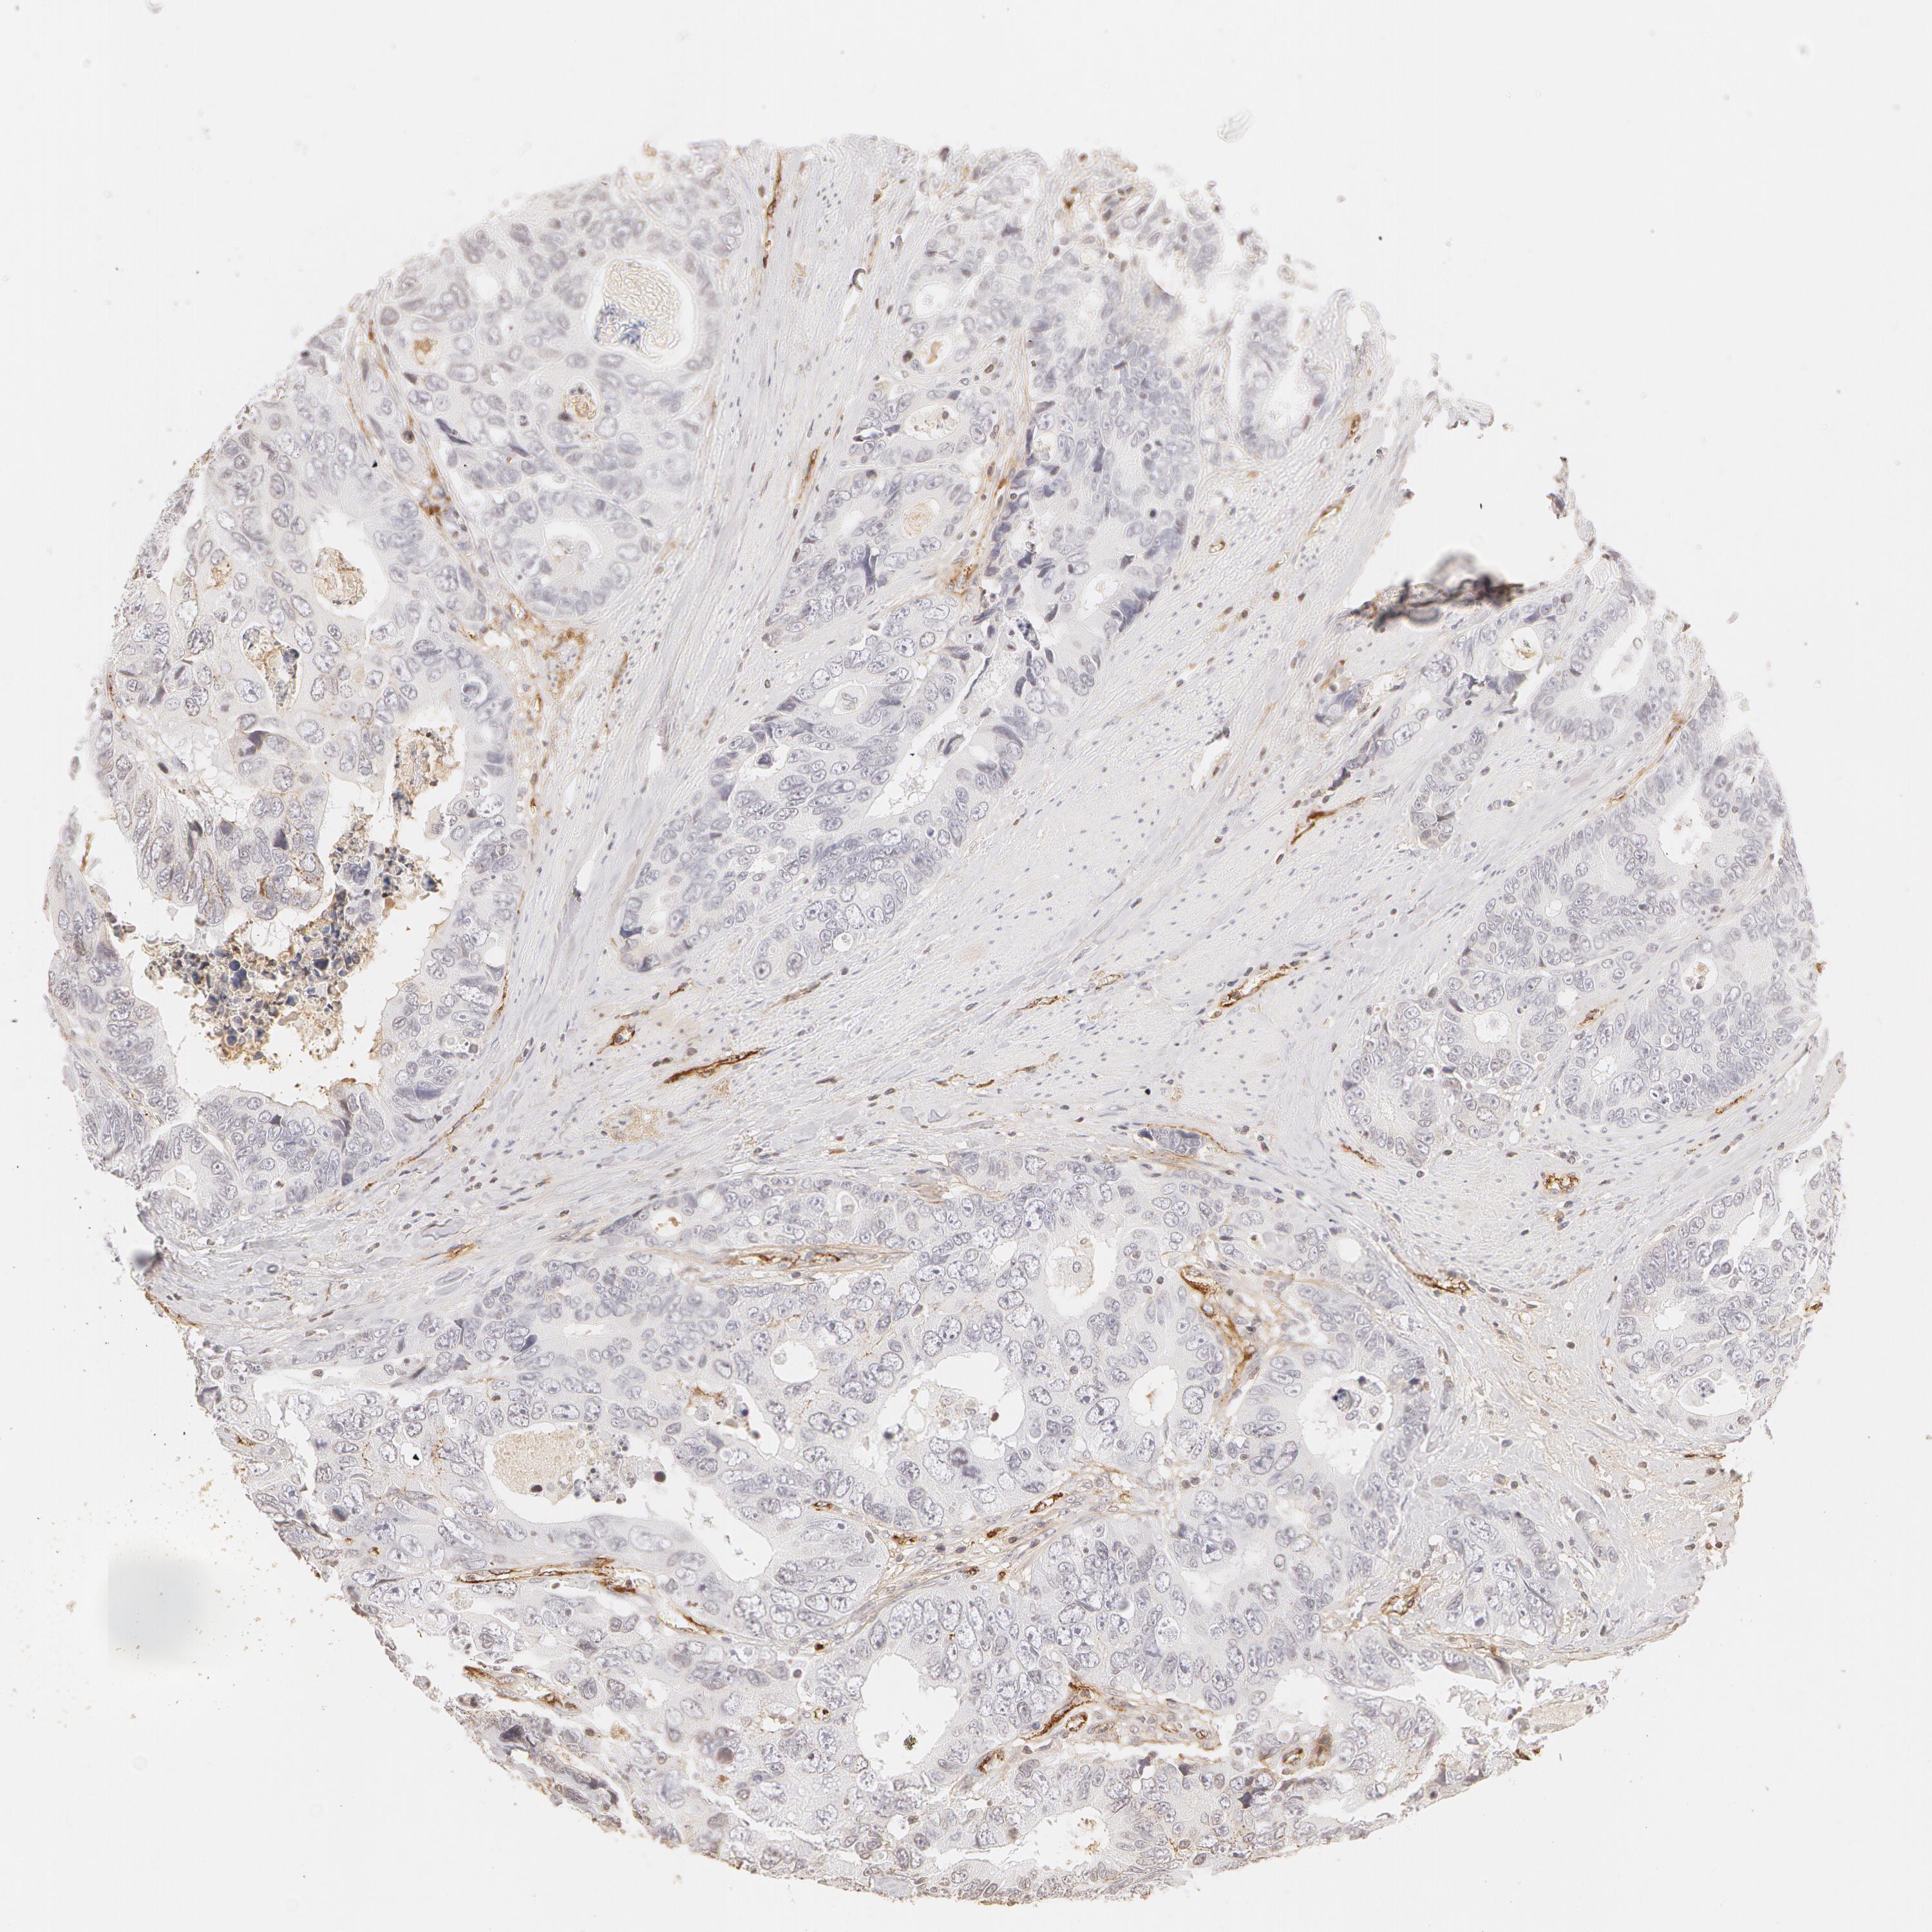

CANCER COLORECTAL CANCER Show tissue menu

ANTIBODIES

AND

VALIDATION